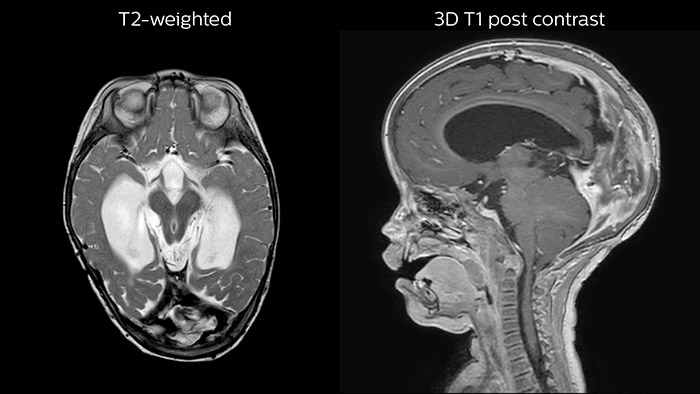

Hydrocephalus post hemorrhagic Both pictures show a ventriculoperitoneal shunt. With our previous scanner our hydrocephalus protocol needed about 25 min. With Ambition the examination time is about 14 min. including a CSF PCA sequence to show flow in the aqueduct.

Since scan times of 3D scans can be significantly shortened thanks to Compressed SENSE, the MRI team is performing more 3D scans than before. “The advantage of 3D scanning is that we capture one high resolution sequence, but we can reconstruct images in any orientation, even after the scan, when looking at the images for diagnosis. Having this ability to view any crosssection we need in high resolution, can make re-scanning unnecessary,” says Dr Junge. “We are currently optimizing our routine head examination to include more 3D scans, including T1- weighted, T2-weighted and FLAIR.”